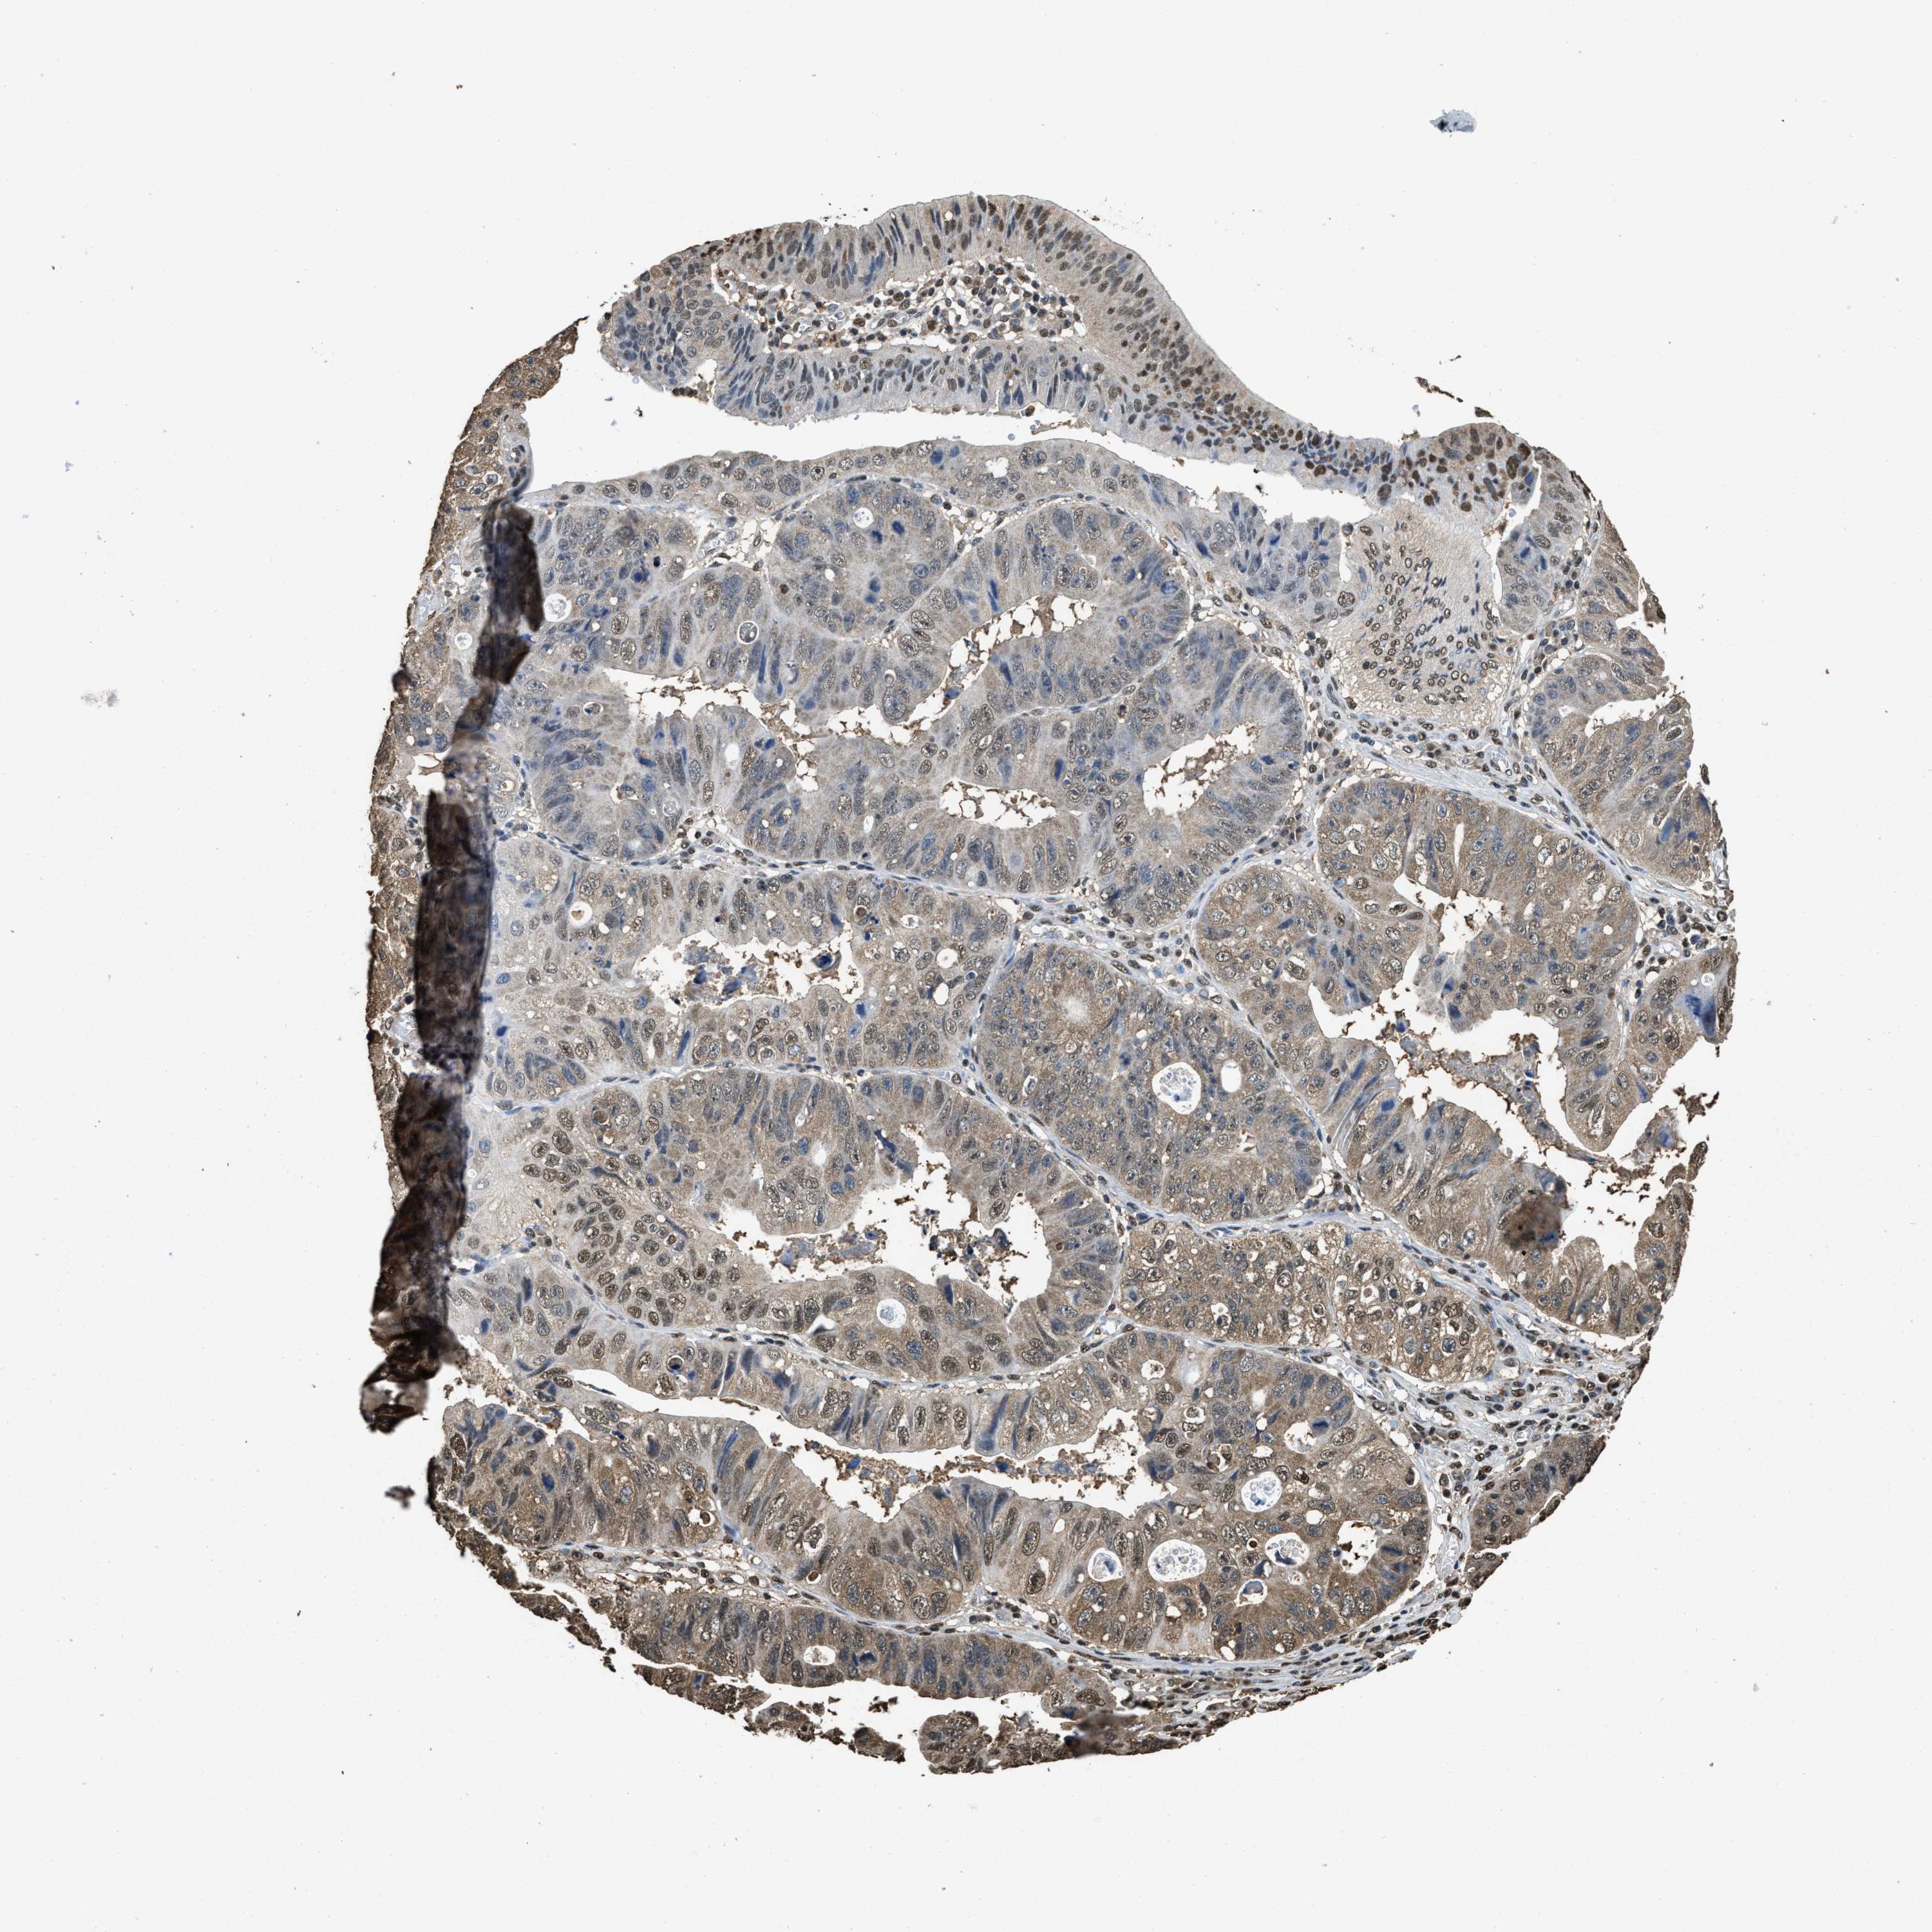

STOMACH CANCER - Protein expressioni

A mouse-over function shows sample information and annotation data. Click on an image to view it in a full screen mode. Samples can be filtered based on level of antibody staining by selecting one or several of the following categories: high, medium, low and not detected. The assay and annotation is described here.

Note that samples used for immunohistochemistry by the Human Protein Atlas do not correspond to samples in the TCGA dataset.

Antibody stainingi

Antibody staining in the annotated cell types in the current human tissue is reported as not detected, low, medium, or high, based on conventional immunohistochemistry profiling in selected tissues. This score is based on the combination of the staining intensity and fraction of stained cells.

Each image is clickable and will lead to virtual microscopy that enables deeper exploration of all samples and also displays staining intensity scores, fraction scores and subcellular localization as well as patient and tissue information for each sample.

HPA040067

HPA061280

CAB005197

CAB016392

CAB079968

Adenocarcinoma, NOS

Adenocarcinoma, High grade